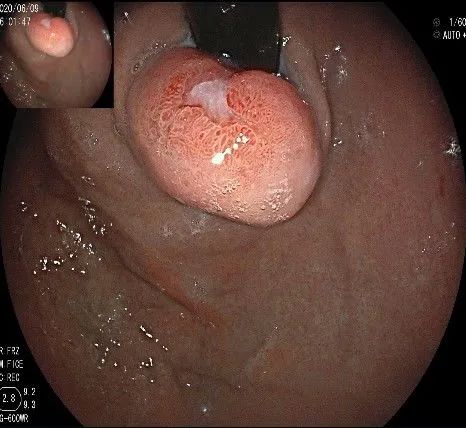

在食管腔内,瘤体的两侧行粘膜下注射后,在瘤体顶部纵向自口侧向肛侧切开食管粘膜。

向下一直切开至齿状线处,白色为鳞状上皮,红色为腺上皮,颗粒样的部分,就是炎性息肉。切开后可见瘤体为白色,表面有血管网,质地较韧。